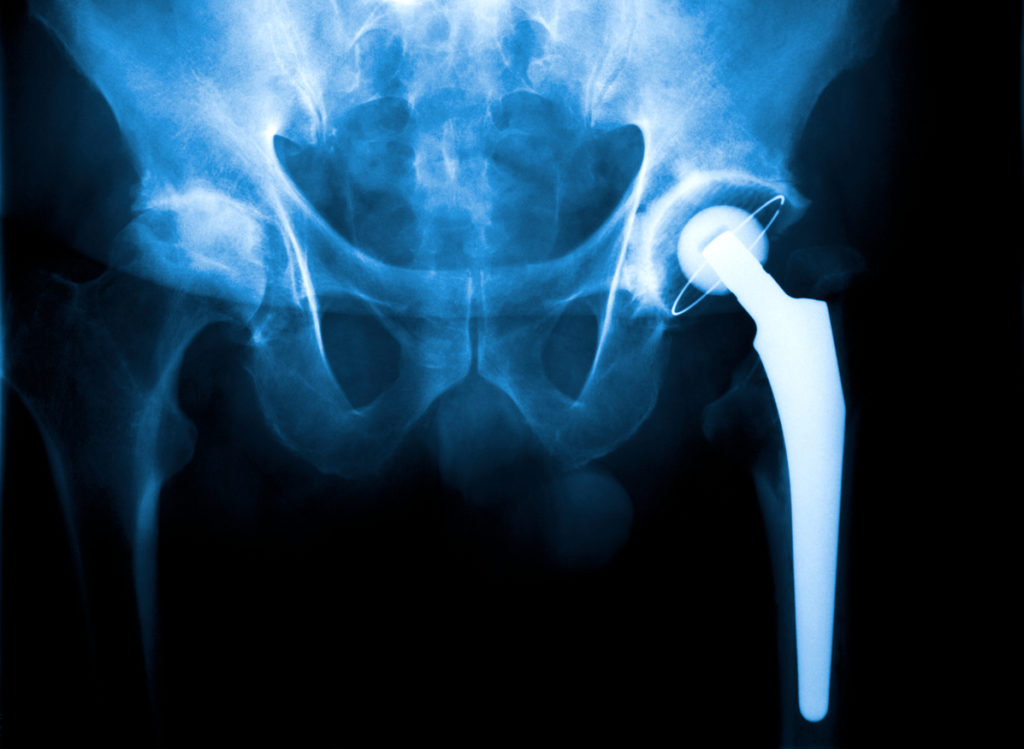

Hip replacement surgery is a common procedure performed in America. This procedure is commonly done on older patients. Hip replacement surgery is executed to alleviate pain and bring back the patient’s mobility and flexibility. There are a variety of reasons why patients may need a hip replacement surgery but the following are the most common.

Orthopedic doctors usually treat this condition with a bone graft. The bone graft allows the surgeon to replace the affected bone with a new and healthy one. Medications may also be prescribed to help manage the pain. If this happens near the joint, joint replacement surgery is more appropriate.

This is a condition that poses a greater risk as we age. Hip injuries may be mild or life-threatening depending on their severity and complexity. Hip fractures are usually treated surgically but may require follow-up physical therapy to ensure proper rehabilitation.

Old injuries, like fractures and tears, may heal improperly. This may cause tissue and bone scarring that complicates the condition. It may also compromise the proper blood flow to the bone and cause bone death and other medical complications.